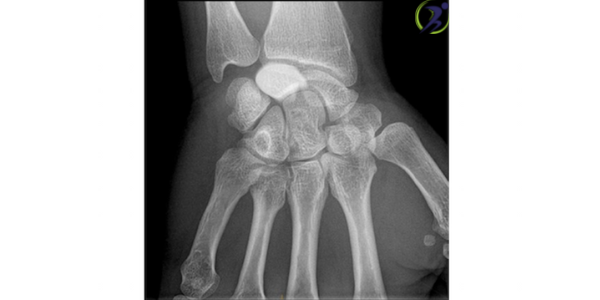

Giai đoạn 2

Xương nguyệt bắt đầu cứng do thiếu nguồn cung cấp máu trong Giai đoạn 2. Quá trình cứng này được gọi là xơ cứng. Ngoài ra, xương nguyệt sẽ sáng hơn hoặc trắng hơn ở những vùng trên phim chụp X-quang, điều này cho thấy xương đang chết. Để đánh giá tốt hơn tình trạng của bệnh, bác sĩ cũng có thể chỉ định chụp MRI hoặc chụp cắt lớp vi tính (CT).

Các triệu chứng phổ biến nhất trong giai đoạn này là đau cổ tay, sưng và đau.